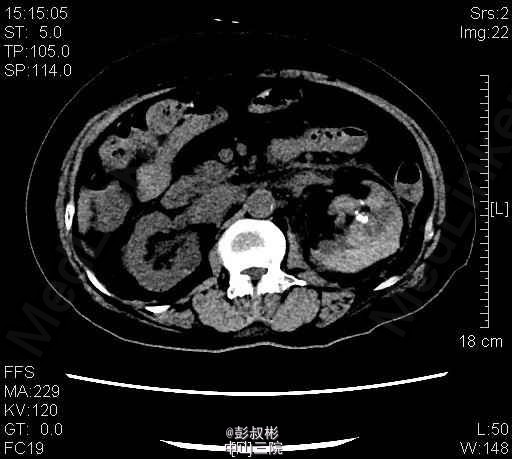

1、患者,女 80岁 2、主诉:左侧腰痛伴发热2天。 3、病史:患者于2天前无明显诱因突发左侧腰痛伴发热,畏寒,最高体温40.1℃,经急诊入院。患者曾于1年前被诊断为“双肾多发结石”,行“左侧经皮肾镜碎石取石术”后好转出院。 4、入院查体:左肾区叩击痛(+),左侧肋脊点、肋腰点压痛(+)。 5、辅助检查:KUB检查示:考虑左输尿管上段结石。B超提示:左肾积脓。胸部正位片:1、双肺纹理增粗,双下胸膜增厚。2、心影增大,主动脉硬化。 6、诊疗过程:患者于入院当晚突发高热、伴寒战、畏寒,最高体温40℃,伴恶心、呕吐,立即予抗感染等治疗。经有效治疗后患者体温有所下降。 随后患者突发抽搐,仍伴寒战、畏寒、意识模糊,予地塞米松10mg静推,加用凡拉蒙2ml肌注,非那根20mg肌注,冬眠灵12.5mg肌注后,控制仍不佳。遂行床边穿刺、抽脓。术后症状有所缓解。术后继续抗感染,患者体温恢复正常,症状明显缓解,无其他不适,遂予出院。